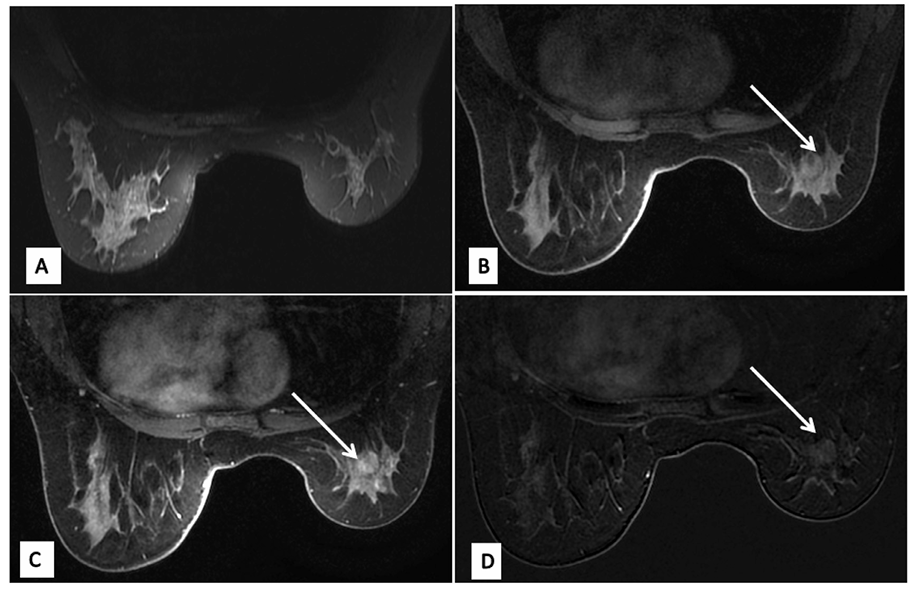

双侧乳腺CE-MRI示双侧乳腺大小不对称,右侧偏小,外上象限见结构扭曲区,无明显弥散受限;增强后呈延迟强化并呈平台型,符合Ⅱ型时间‑信号强度曲线

图2 双侧乳腺CE-MRI